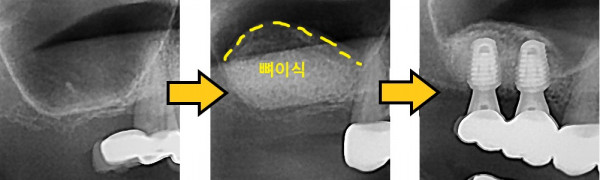

임플란트 뼈이식 + 임플란트